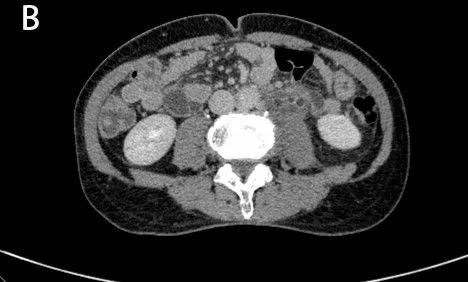

图1A、B:CT平扫示左肾及左侧输尿管扩张积水。

图2A

图2B

图2A、B:CT增强扫描呈双环及双腔改变 ,早期可见外腔密度增高。